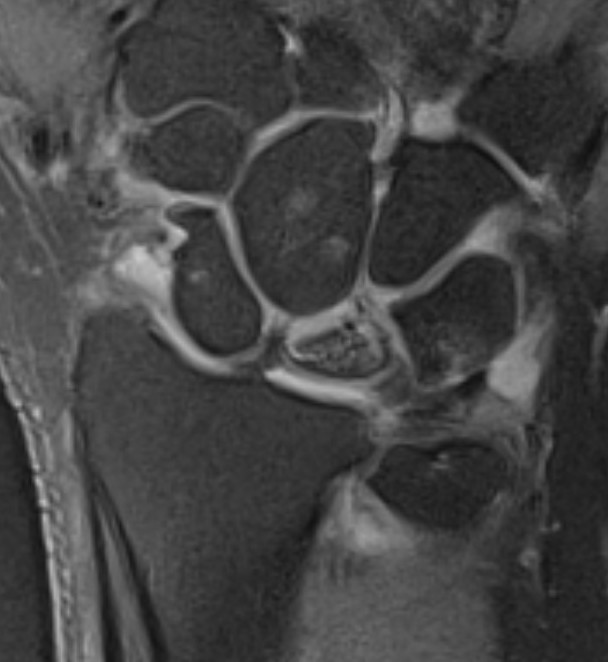

MRI

Avascular lunate on MRI

Avascular lunate with some cystic change on the capitate